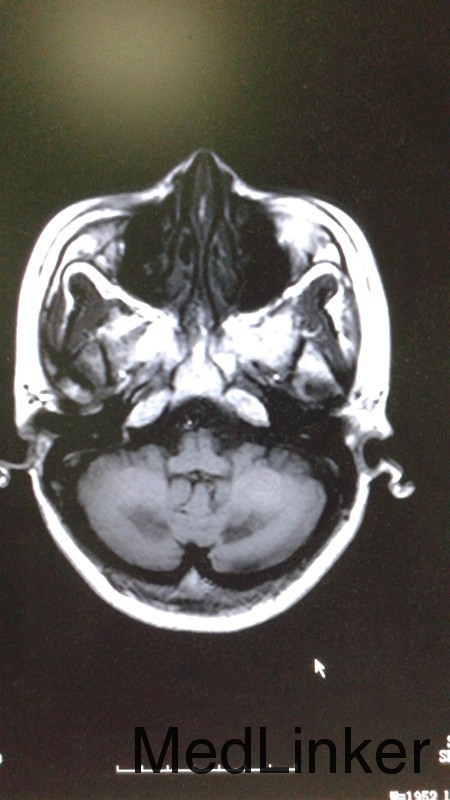

患者,女,44岁。主因反应迟钝,行走不稳4年,加重伴吞咽困难8月 患者4年前无明显诱因出现表情淡漠、反应迟钝,不与人交流,嗜睡、懒动、乏力,不修边幅,期初不影响生活未予诊治。此后上述症状逐渐加重,与人交流日渐减少,嗜睡,至两年前逐步出现行走左摇右摆,言语表达含糊不清,难以胜任日常生活,遂入院治疗,期间行头颅MRI示:1、双侧小脑齿状核、大脑脚及皮质脊髓束对称性异常信号。行跟腱检查结果示:左足纤维组织内查见结晶炎物及泡沫细胞,右足跟腱组织活检病理诊断:纤维结缔组织可见较多胆固醇裂隙、多核巨细胞形态符合黄色瘤,给予熊去氧胆酸片口服后病情好转出院。症状有所改善。服药期间自行停药。8个月前无明显诱因出现言语不利,行走不稳症状再次加重,双下肢僵硬、无力,行走不稳,需与人搀扶,遂再次入院。